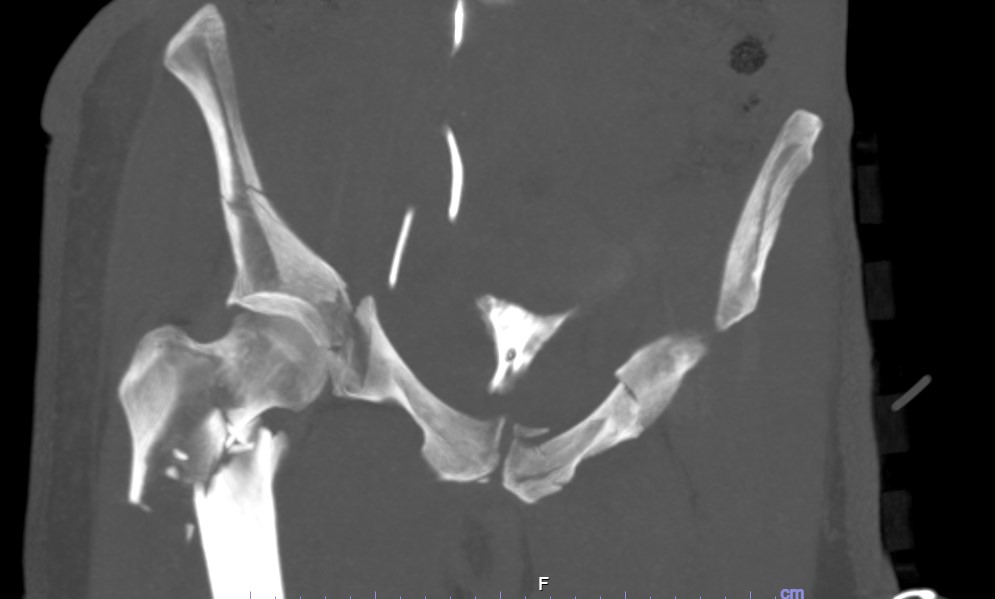

FRACTURA DE PELVIS Y ACETÁBULO

La pelvis conecta la columna con las piernas y soporta el peso del cuerpo. Puede fracturarse por traumatismos graves o por osteoporosis.

El acetábulo es la parte de la pelvis que forma la cavidad donde encaja la cabeza del fémur, formando la articulación de la cadera.

Algunas fracturas sanan con reposo, pero otras necesitan cirugía.